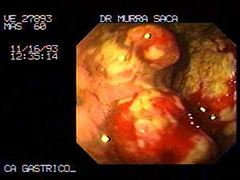

Imagen Endoscópica de extenso carcinoma obstructivo masculino 60 años:

-

Imagen endoscópica del mismo paciente descrito anteriormente con extenso carcinoma de cuerpo y antro.